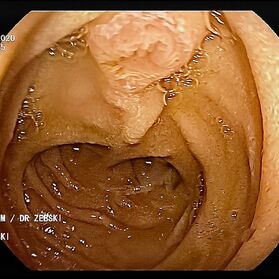

Mit einer Gastroskopie werden Speiseröhre, Magen und Zwölfingerdarm (der oberste Teil des Dünndarms) untersucht. Dazu wird ein geschmeidig biegsames, schlankes Endoskop mit eingebauter Digitalkamera durch den Mund eingeführt. Minimalste Veränderungen können dabei gesehen werden, die im Röntgenbild oder einer Kernspintomographie (MRT) noch gar nicht erkannt werden. Im Vergleich zu anderen bildgebenden Untersuchungsverfahren ist bei der Endoskopie neben der wichtigen optischen Beurteilung auch die sofortige Möglichkeit gegeben, Gewebeproben aus auffälligen Bereichen zu entnehmen. Dazu wird eine kleine Spezialzange durch einen Kanal im Endoskop geschoben und die Probe ganz präzise aus dem entsprechenden Gewebe gewonnen. Da die Schleimhäute schmerzunempfindlich sind, spüren Sie davon nichts. Die Proben werden von Spezialisten mikroskopisch untersucht und ermöglichen dann eine zielgerichtete Therapie; zum Beispiel wenn eine Magenschleimhautentzündung durch eine chronische Infektion ausgelöst wird, die mit einer Antibiotikakur erfolgreich behandelt werden kann.